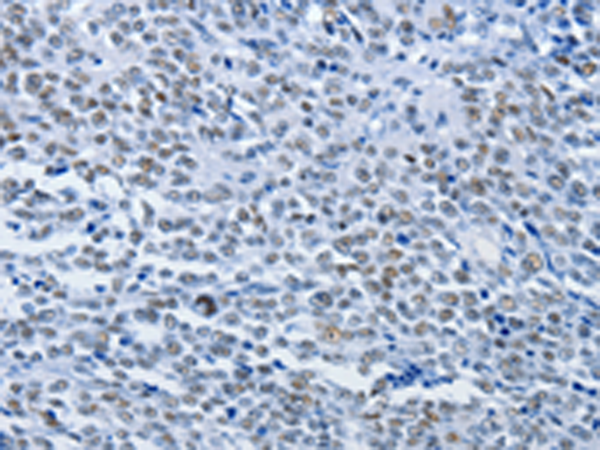

分类: 科研抗体货号: P10734别名: CBX; M31; MOD1; p25beta; HP1-BETA; HP1Hsbeta; HP1Hs-beta应用: IHC反应种属: Human, Mouse